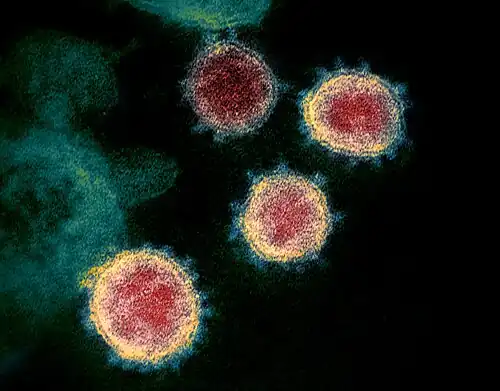

TEM image of SARS-CoV-2, the coronavirus responsible for COVID-19: PMIS / MIS-C is thought to be caused by an unusual biological response to infection in certain children | |